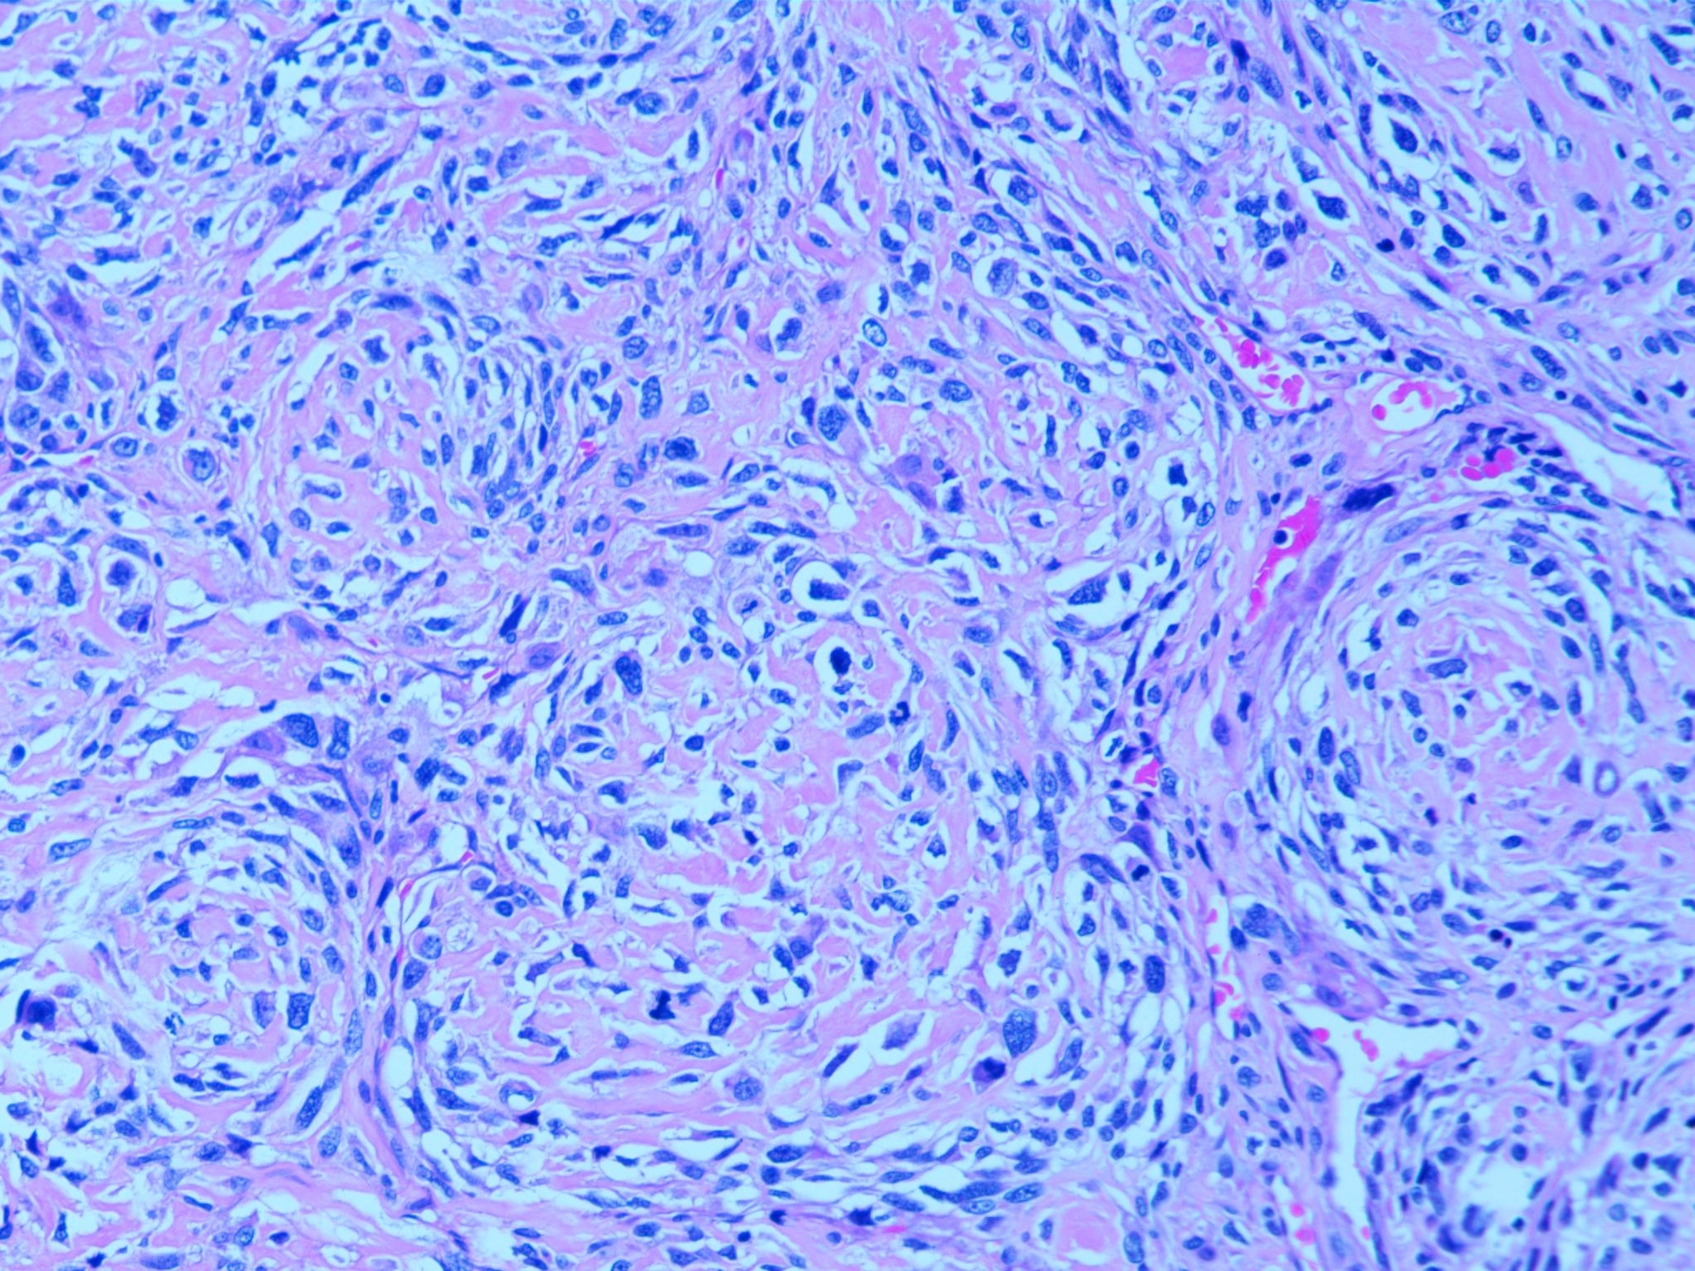

梭形细胞恶性肿瘤,可见肿瘤性成骨,结合活检免疫组化,考虑为普通型骨肉瘤,高级别,骨断端及四周切缘均阴性。

免疫组化结果:SMA +,Desmin -,MyoD1 胞浆+,Myogenin -,Ki-67 80%+,CD34 血管+,STAT6 胞浆+,S-100 -,SOX10 部分+,H3.3 G34W -,SATB2 +,H3K27Me3 未缺失,INI-1 未缺失,CD31 -,ERG -,Fli-1 -。